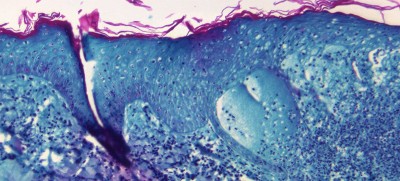

The World Health Organization (WHO) chief said on Wednesday that monkeypox infections in non-endemic countries have passed the 1,000 mark and the risk of it becoming established in some is “real”.

Monkeypox: Canadian travellers abroad asked to be cautious, new isolation measures issued

Jun 09, 2022, at 04:57 am

800 Monkeypox cases detected in 27 non-endemic countries: WHO

Jun 06, 2022, at 02:25 am

Geneva/UNI/Sputnik: At least 780 confirmed monkeypox cases were identified in humans in 27 non-endemic countries from May 13 to June 2, the World Health Organization (WHO) said.